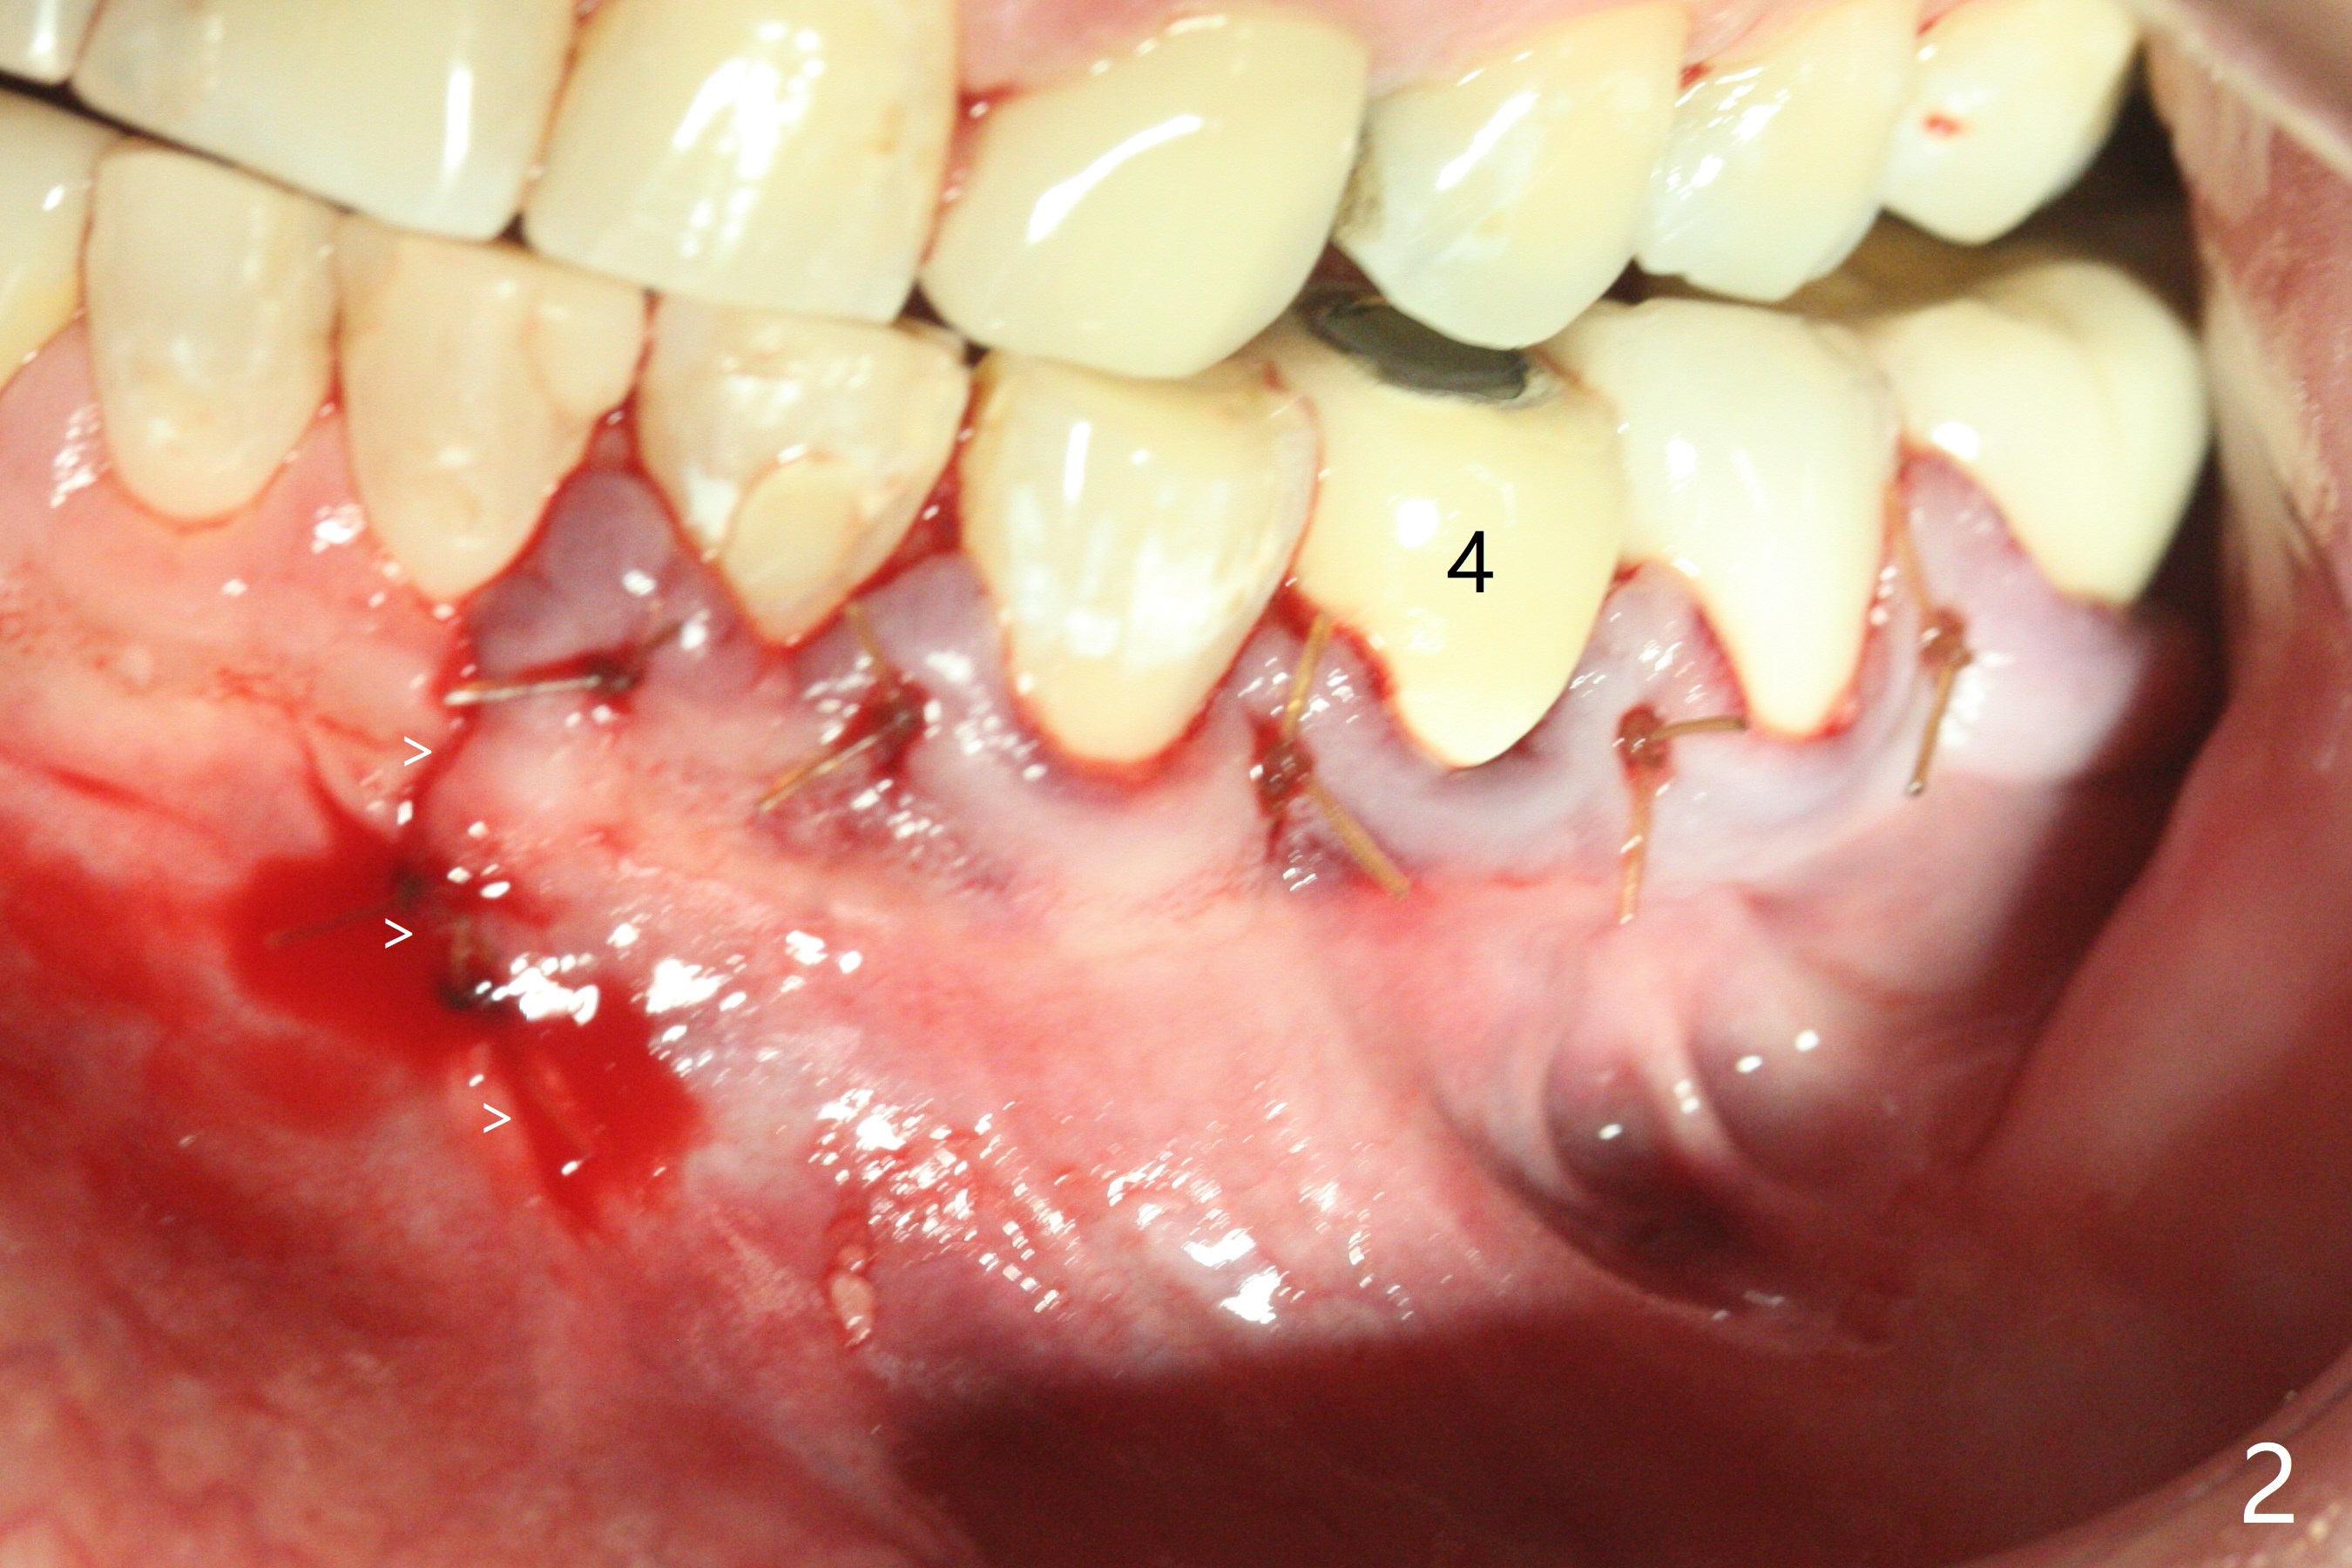

术前冷和电牙髓活力测定显示左下3活髓,不得不做一个长切口和附加切口(图二:>),在暴露颏神经后,在4根尖做囊肿切除术(图一),好像上颌窦外提升,使用上颌窦提升术器械才把囊肿挖出来,不同之处是颊侧骨壁特别厚,为了容易去除4根尖舌侧囊肿,做了根切(图三:<,与图三 ' (术前)对比),但是没做倒充,觉得根管充填完整。并且填入不少粘性骨块(图三)。病理报告:Left Mandibular Body, #21, Excisional Biopsy: Benign fibrous and granulation tissue with acute and chronic inflammation, consistent with periapical granuloma. Negative for odontogenic keratocyst and unicystic ameloblastoma. 左下颌骨体部,21号牙,切除性活检:良性纤维和肉芽组织伴有急性和慢性炎症,与根尖周围肉芽肿一致。牙源性角化囊肿和单房性造釉细胞阴性。术后两个月伤口愈合(图四),骨粉好像安居乐业(图五:*)。